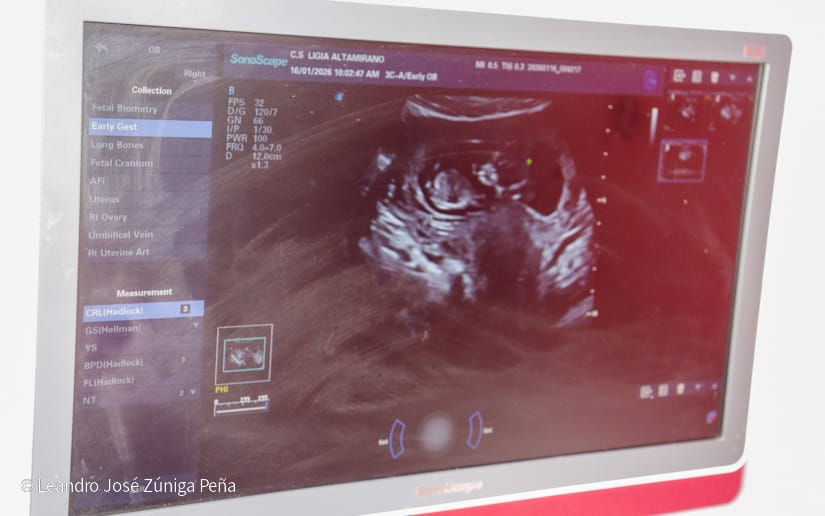

Con el objetivo de detectar afectaciones durante el proceso de embarazo, más de 100 mujeres fueron atendidas este viernes en una feria de salud desarrollada en el Centro de Atención a la Mujer Dra. Ligia Altamirano

“Todo esto se hace con el objetivo de disminuir las complicaciones, tanto maternas como neonatales que son la base fundamental de nuestra sociedad y que van ayudar a la mujer a tener un embarazo sin complicaciones y con menor gasto, ya que todos estos estudios son completamente gratuitos”, manifestó la Directora de la casa materna, doctora Judith García.